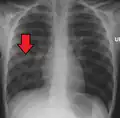

| Chest X-ray of a pneumonia caused by influenza and Haemophilus influenzae, with patchy consolidations, mainly in the right upper lobe (arrow) | |